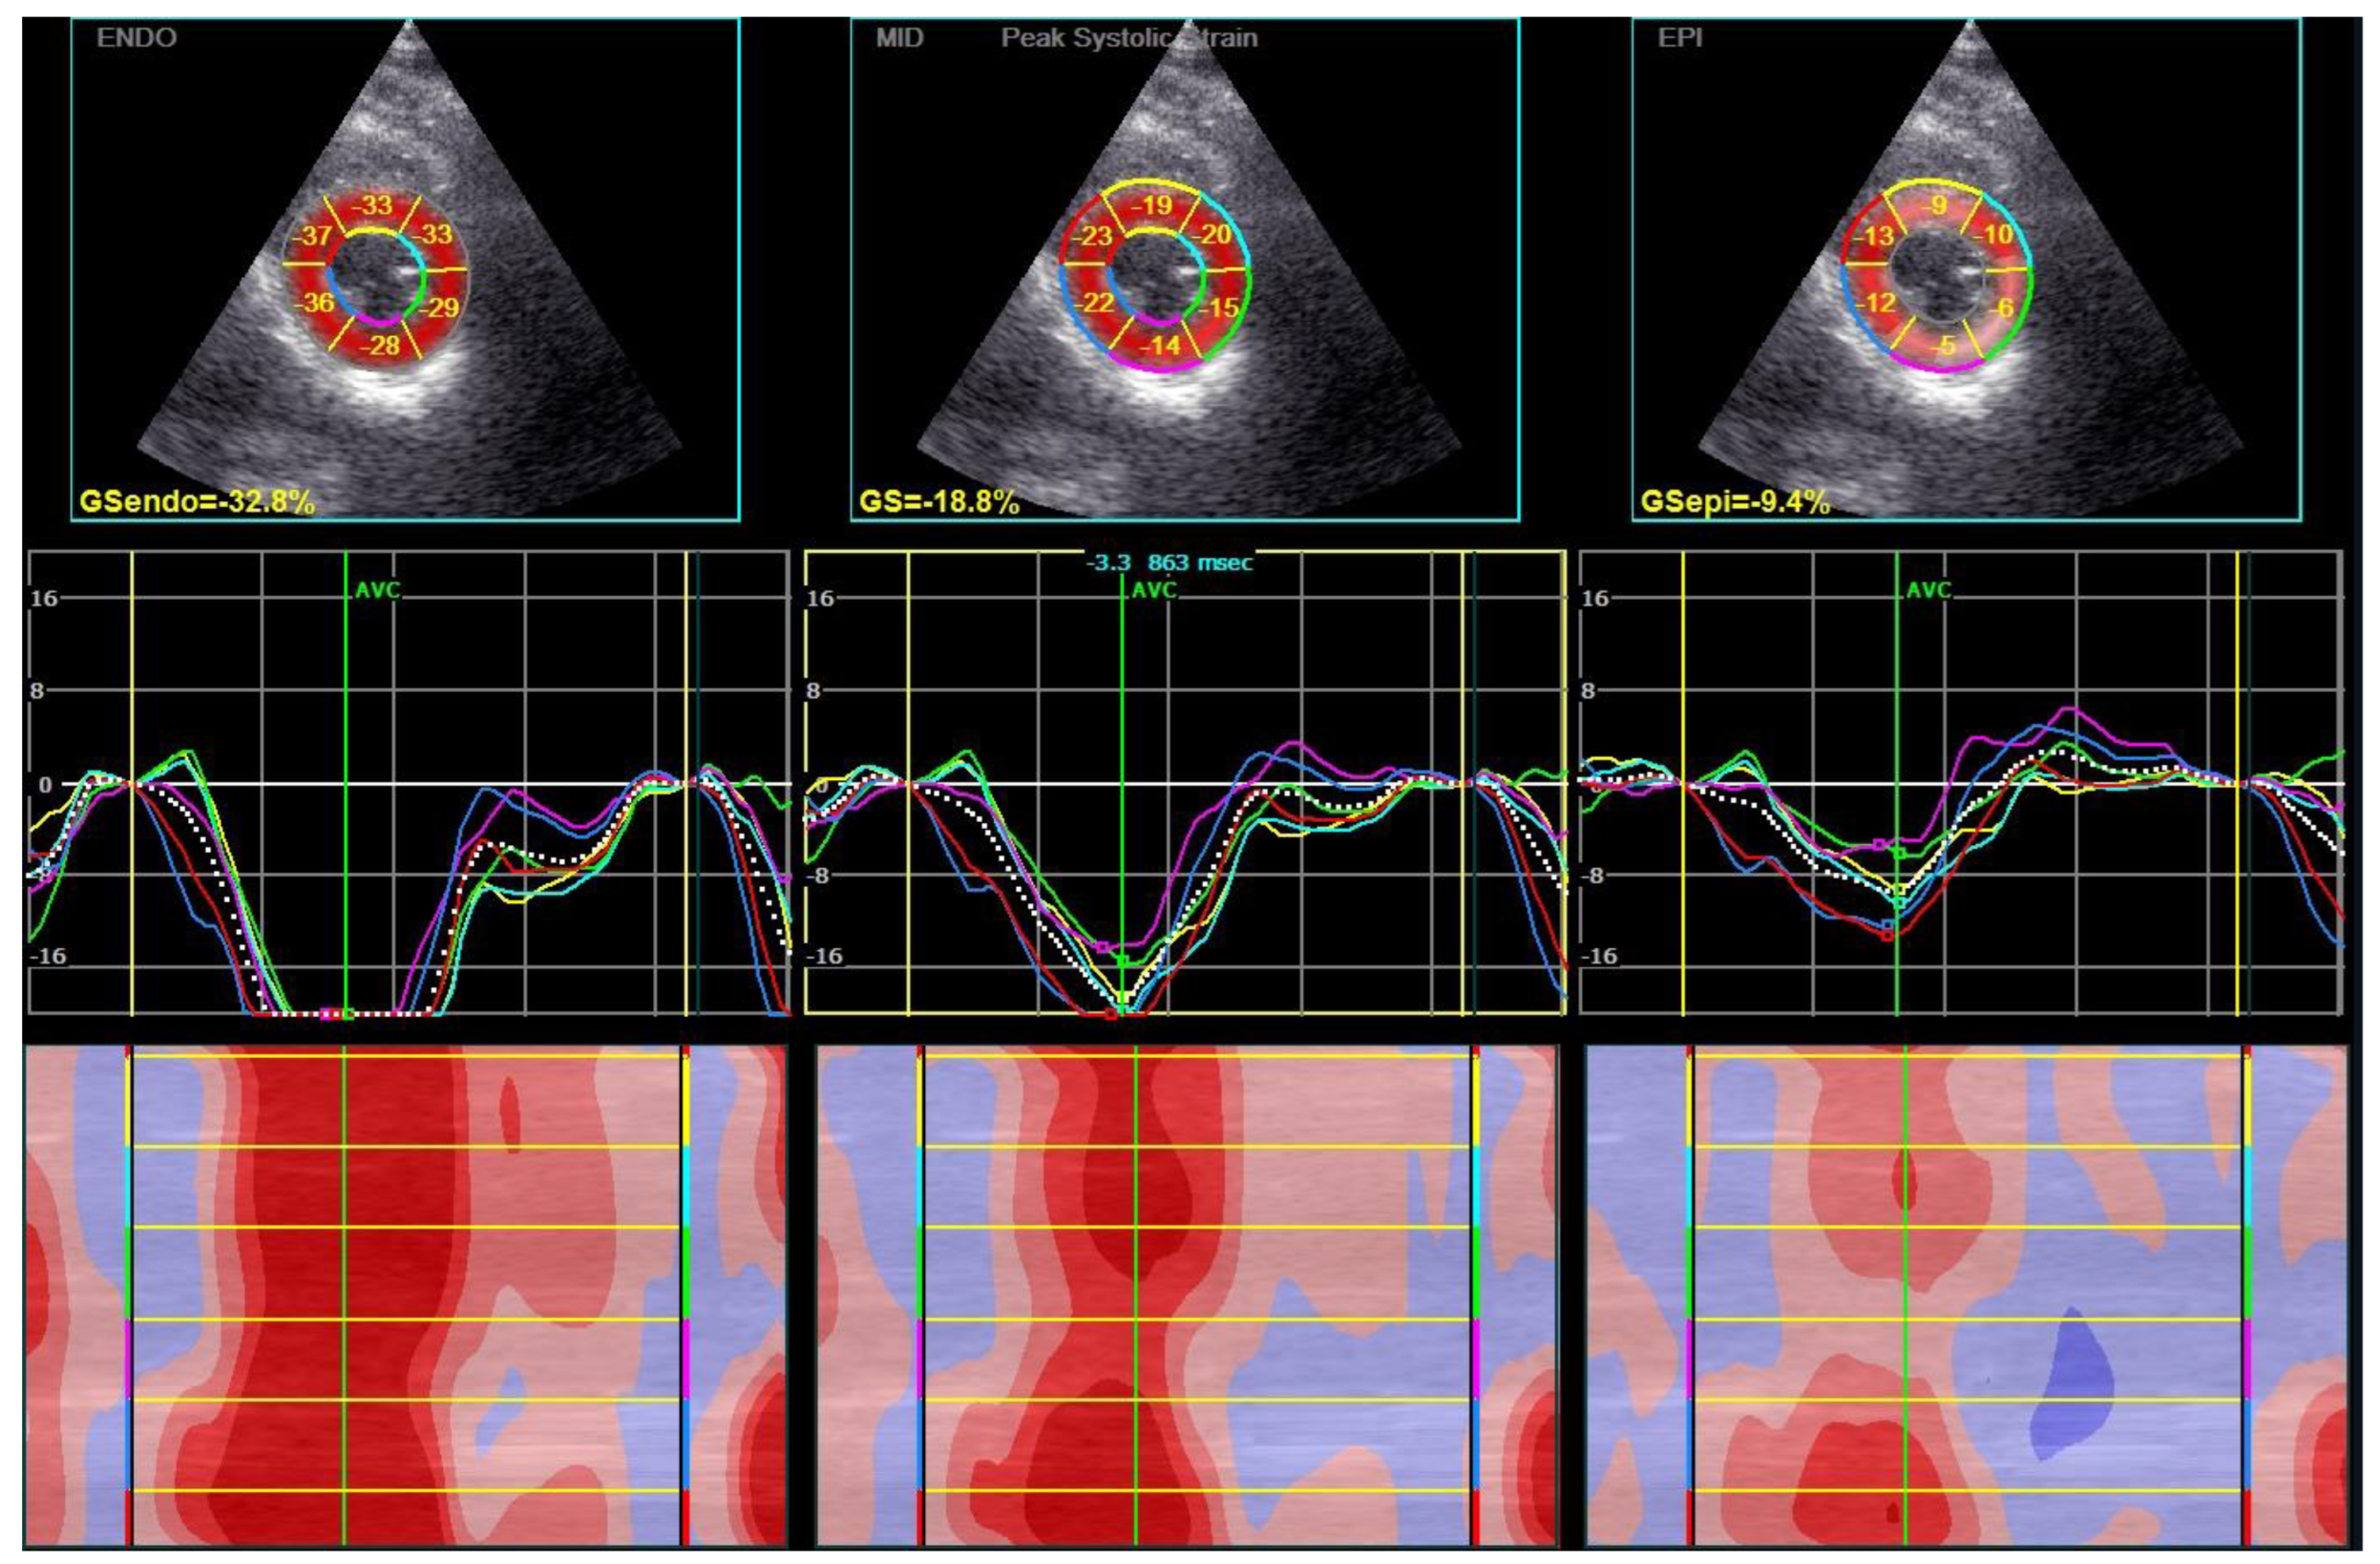

2.4. Two-Dimensional Speckle-Tracking Echocardiography

| GCS, % | epicardial | −9.2 (−11.7, −9.2) | −8.8 (−11.2, −6.8) | −10.2 (−12.1, −7.6) | 0.348 |

| mid-wall | −14.9 (−17.2, −11.1) | −15.1 (−17.1, −11.1) | −14.9 (−17.2, −11.8) | 0.824 | |

| endocardial | −24.8 (−29.0, −18.5) | −24.3 (−29.7, −18.8) | −25.3 (−27.6, −18.4) | 1.000 | |

| average | −16.4 (−18.8, −11.8) | −16.2 (−18.9, −11.8) | −16.4 (−18.4, −13.5) | 0.962 | |